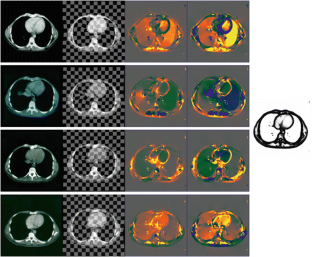

In this chapter we are concerned with variational methods in image analysis. Special attention is paid on free discontinuity approaches of Mumford Shah type and their application in segmentation, matching and motion analysis. We study combined approaches, where one simultaneously relaxes a functional with respect to multiple unknowns. Examples are the simultaneous extraction of edges in two different images for joint image segmentation and image registration or the joint estimation of motion, moving object, and object intensity map. In these approaches the identification of one of the unknowns improves the capability to extract the other as well. Hence, combined methods turn out to be very powerful approaches. Indeed, fundamental tasks in image processing are highly interdependent: Registration of image morphology significantly benefits from previous denoising and structure segmentation. On the other hand, combined information of different image modalities makes shape segmentation significantly more robust. Furthermore, robustness in motion extraction of shapes can be significantly enhanced via a coupling with the detection of edge surfaces in space time and a corresponding feature sensitive space time smoothing. Furthermore, one of the key tools throughout most of the methods to be presented is nonlinear elasticity based on hyperelastic and polyconvex energy functionals. Based on first principles from continuum mechanics this allows a flexible description of shape correspondences and in many cases enables to establish existence results and one-to-one mapping properties. Numerical experiments underline the robustness of the presented methods and show applications on medical images and biological experimental data. This chapter is based on a couple of recent articles (Bar et al., A variational framework for simultaneous motion estimation and restoration of motion-blurred video, 2007; Litke et al., An image processing approach to surface matching, 2005; Droske et al., Comput. Vis. Sci. Online First, 2008; Droske and Rumpf, SIAM Appl Math 64(2):668–687, 2004; Droske and Rumpf, IEEE Trans Pattern Anal Mach Intell 29(12):2181–2194, 2007; Rumpf and Wirth, SIAM J Imag Sci, 2008) published by the author together with Leah Bar, Benjamin Berkels, Marc Droske, Nathan Litke, Wolfgang Ring, Guillermo Sapiro, Peter Schröder, and Benedikt Wirth.

The author is grateful to Werner Bautz, radiology department at the university hospital Erlangen, Germany, for providing CT data of kidneys, as well as to Heiko Schlarb from Adidas, Herzogenaurach, Germany, for providing 3D scans of feet, and to Bruno Wirth, urology department at the Hospital zum Hl. Geist, Kempen, Germany, for providing thorax CT scans. Furthermore, the author thanks Stan Osher for pointing to the issue of elastic shape averaging and Marc Droske for discussion about the phase field approach. Finally, he acknowledges Helene Horn for her help in the careful preparation of the manuscript.